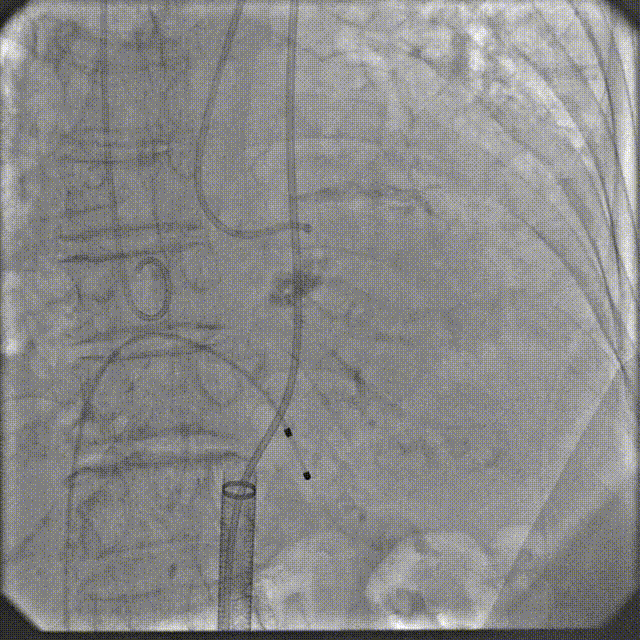

手术过程

根部造影

跨瓣

定位造影

球扩

释放

最终造影

术后复查造影示瓣膜位置满意,形态良好,冠脉显影良好;TTE示轻微瓣周漏;排除入路血管问题,手术圆满成功。